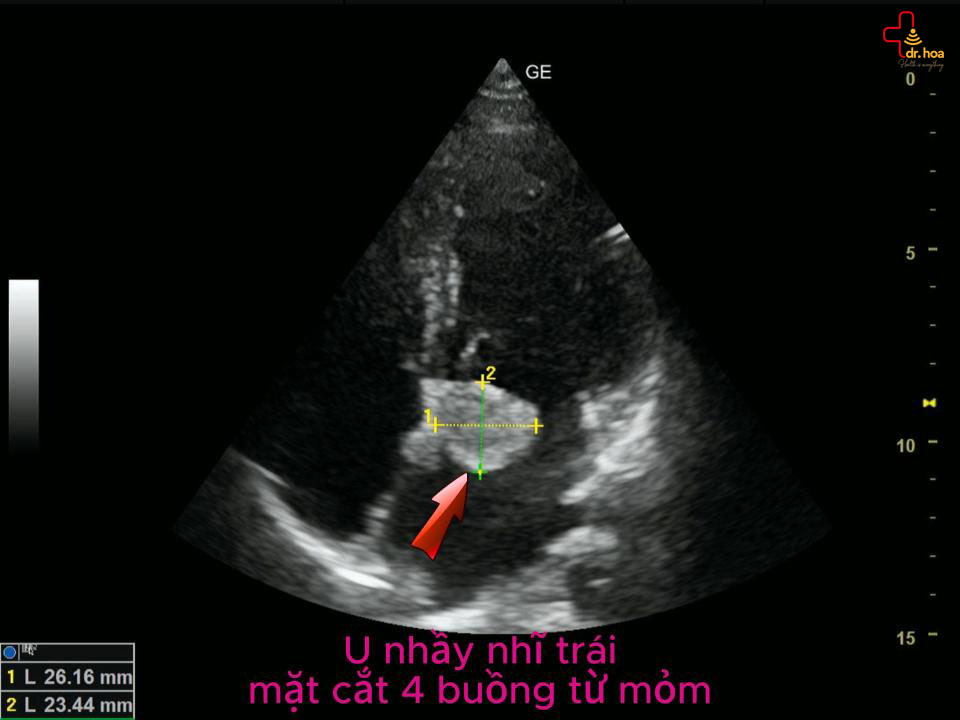

Sau khi thăm khám lâm sàng, bác sĩ thường chỉ định thêm các phương pháp cận lâm sàng nhằm chẩn đoán chính xác u nhầy trong tim và đánh giá mức độ ảnh hưởng của khối u: U nhầy nhĩ trái, mặt cắt 4 buồng từ mỏm. U nhầy nhĩ trái, mặt cắt 4 buồng từ mỏm.

• Siêu âm tim:

Đây là kỹ thuật quan trọng và được sử dụng phổ biến nhất. Siêu âm tim giúp xác định rõ vị trí, kích thước, chỗ bám cũng như đặc điểm cấu trúc của khối u nhầy (có thể đồng nhất, chứa nang hoặc vôi hóa). U nhầy nhĩ trái, động mạch chủ cắt ngang. U nhầy nhĩ trái, động mạch chủ cắt ngang.

Bác sĩ có thể thực hiện siêu âm tim qua thành ngực hoặc qua thực quản để tăng độ chính xác, đặc biệt trong việc đánh giá các khối u nhầy nhỏ và mức độ ảnh hưởng đến van tim.U nhầy nhĩ trái, mặt cắt 4 buồng từ mỏm không tín hiệu Doppler. U nhầy nhĩ trái, mặt cắt 4 buồng từ mỏm không tín hiệu Doppler.